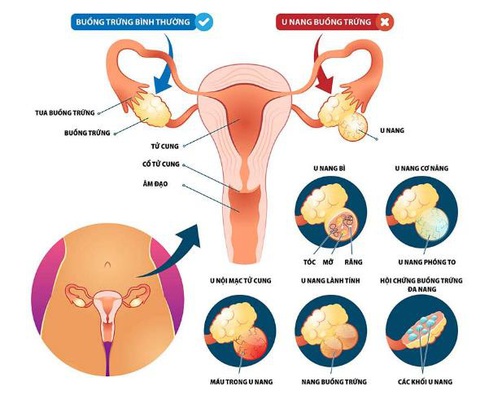

U nang buồng trứng đa số là lành tính, chỉ một số trường hợp u biến chứng thành ung thư - Ảnh: BVCC

BS.CKII. Ngô Minh Nghĩa - cố vấn chuyên môn Bệnh viện Tâm Trí Cao Lãnh - cho biết u nang buồng trứng đa số là lành tính. Tuy nhiên, một số trường hợp u biến chứng thành ung thư. Nếu không được điều trị sớm sẽ ảnh hưởng đến sức khỏe và tính mạng của bệnh nhân.

U buồng trứng có thể gặp ở mọi lứa tuổi kể cả trẻ em và người mãn kinh. Thông thường hay gặp ở nữ giới trong tuổi sinh sản.